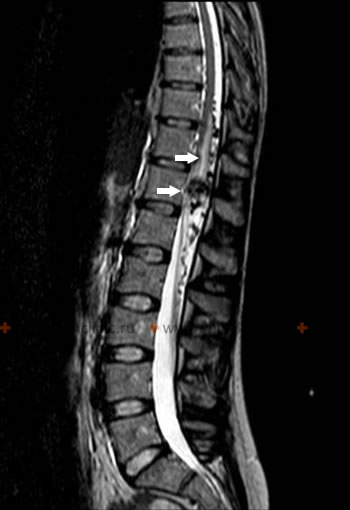

При магнитно-резонансной томографии (МРТ) пояснично-крестцового отдела позвоночника 3,0 Т (тесла) врач получает возможность не только исследовать структурные и патологические изменения позвоночника на МРТ, но и оценить физико-химические, патофизиологические процессы как всего спинного мозга в целом, так и его отдельных структур (нервных корешков). Магнитно-резонансная томография (МРТ) пояснично-крестцового отдела позвоночника позволяет так же проводить функциональные исследования спинного мозга, выполнять магнитно-резонансную ангиографию его артерий, не требующую прямой пункции сосуда (как при селективной ангиографии).

Магнитно-резонансная томография (МРТ) позвоночника 3,0 Т (тесла) позволяет получить серию тонких срезов, построить трехмерную реконструкцию исследуемого отдела позвоночника. При магнитно-резонансной томографии (МРТ) позвоночника можно выделить сосудистую сеть, визуализировать связки и эпидуральное пространство (важно при эпидурите) и даже отдельные нервные стволы, выходящие из спиномозгового канала.

В плане дифференциальной диагностики при магнитно-резонансной томографии (МРТ) позвоночника большое значение имеет получение поперечных срезов на разных его уровнях, как при обнаруженном стенозе позвоночного канала и т.д.